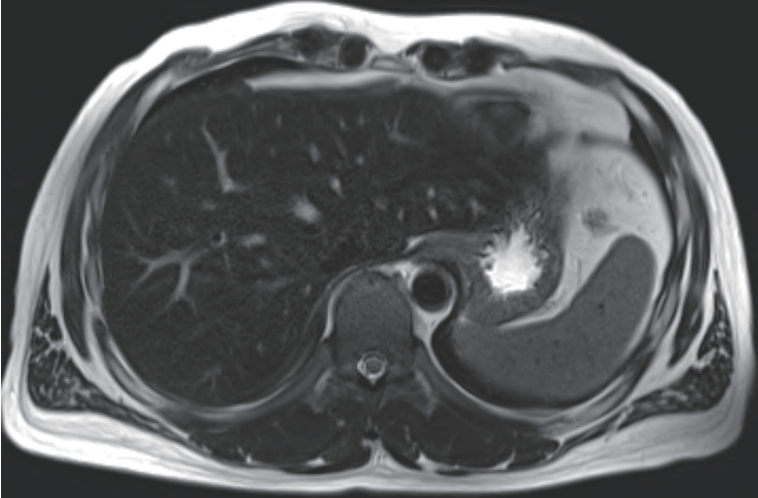

Acute hepatitis A is an inflammation of the liver caused by the hepatitis A virus, typically resulting in mild to severe illness from which most individuals recover fully without complications. However, in rare cases, it may lead to long-term sequelae. Secondary hemochromatosis refers to iron overload resulting from various causes, including chronic liver disease, repeated blood transfusions, and systemic inflammation. Here, we report a rare case of secondary hemochromatosis that developed following acute hepatitis A.

Recently, the survival benefit of immuno-oncologic (IO) agents for advanced hepatocellular carcinoma (HCC) has been proven in several randomized controlled trials. Especially, atezolizumab with bevacizumab (Ate+Beva), as a first-line therapy for advanced HCC, has shown outstanding efficacy in the IMBrave150 study. Fortunately in south Korea, the cost of Ate+Beva therapy can be covered by national medical insurance, therefore HCC patients can receive Ate+Beva therapy without trouble. However, almost all HCC patients have no choice but to stop the treatment after two years completion of Ate+Beva therapy because our national medical insurance only cover IO therapy for two years. Therefore clinicians have been restarting the systemic treatment after confirming the disease progression of HCC patients on resting period of systemic therapy. Here, we report a case that showed a partial response of lymph node metastasis by 3rd line regorafenib therapy for progression of LN metastasis after achieving nearly complete response by two-year completion of 1st line Ate+Beva therapy in advanced HCC patient.